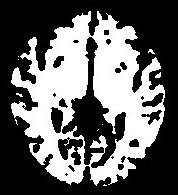

An illustration of the process at the level of a slice:

You can for instance visualize simultaneously the bias corrected image and the brain mask, relying on Anatomist linked cursor:

Another way consists of the two volume fusion. brainVISA's eye can do it for you. If you prefer manual work, select the two volumes, give a unicolor colormap with the ufusion extension to the mask, and choose the linear combination fusion mode: